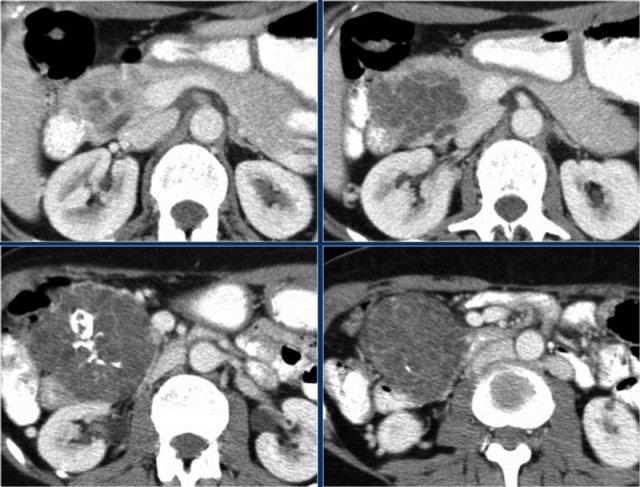

Cuộn qua các hình ảnh.

Ở đuôi tụy có tổn thương dạng nang với sẹo trung tâm kèm vôi hóa (mũi tên).

Mặc dù một số nang có kích thước lớn hơn 2 cm, hình ảnh này vẫn điển hình cho u nang tuyến thanh dịch, do có sẹo trung tâm, hình ảnh đa thùy và bờ viền thùy múi.

Bệnh nhân này có các triệu chứng đau bụng được quy cho khối u, khối u đã được phẫu thuật cắt bỏ và kết quả giải phẫu bệnh xác nhận là u nang tuyến thanh dịch.

Đây là bệnh phẩm sau phẫu thuật cắt bỏ.

Khối u dính vào lách, do đó lách cũng phải được cắt bỏ cùng.